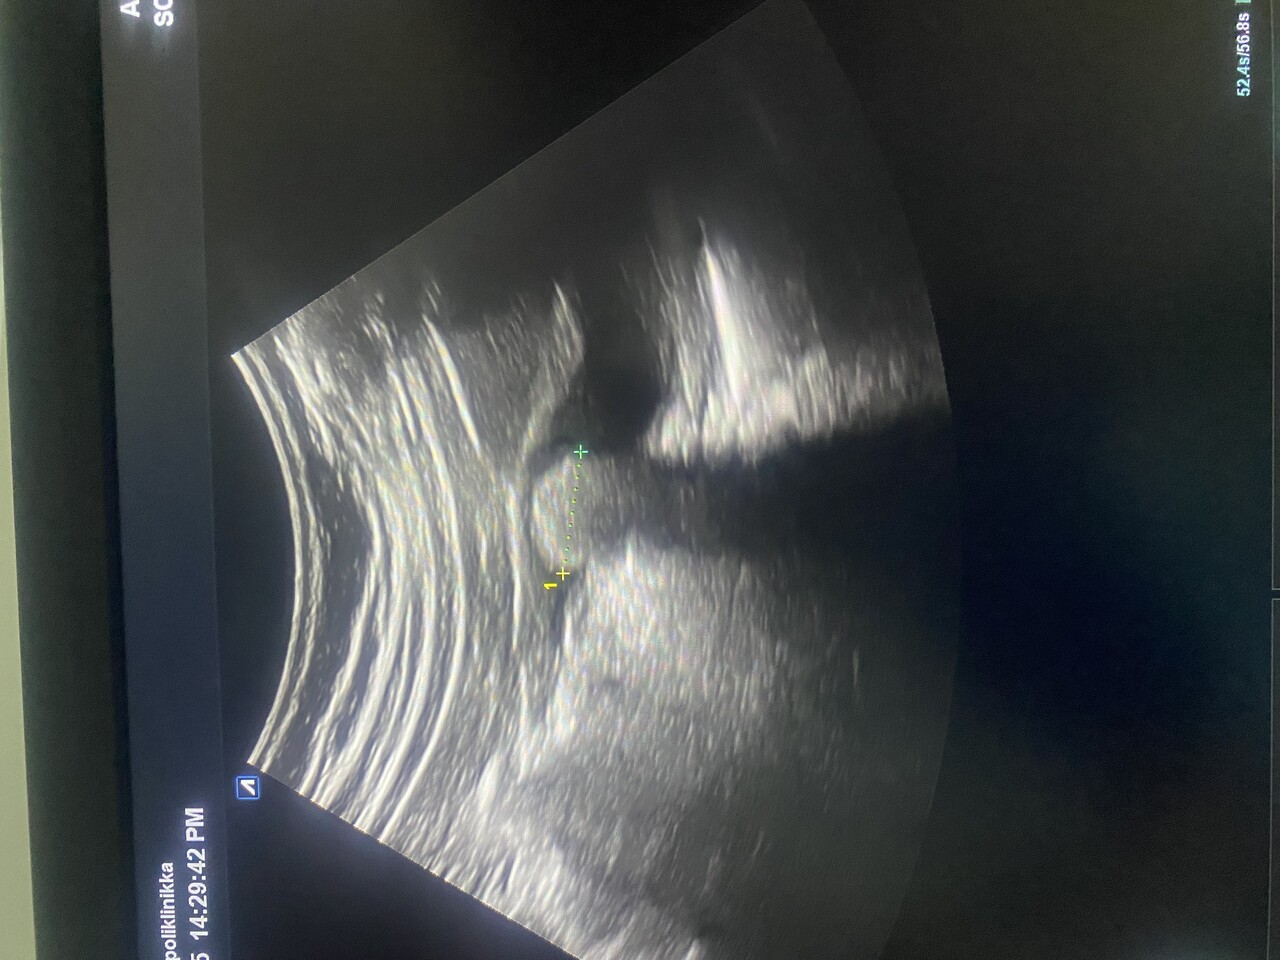

Если эта смерть в яйце… то есть в желчном пузыре меня рань ше не прикончит. 18 мм .

Но желчный плохо наполнен надо бы переделат, я ж сам себе без спросу сделал.

Мож и артефакт какой, хз.